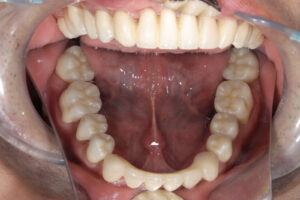

セラミック治療

費用

4,968,000円(税込み)

内:オールセラミック1本/120,000円、

治療期間

2年

通院頻度

1ヵ月 2~3回

初診日 2016. 12.  (5年経過症例)

治療結果

審美的な仕上がりで、患者自身も満足した。5年経過し良好である。

現在は2〜3ヶ月おきのメインテナンス中である。

オールセラミックには欠け易いといったリスクがあるためナイトガードは必須である。

特に清掃が重要である。

ナイトガードは必須である。